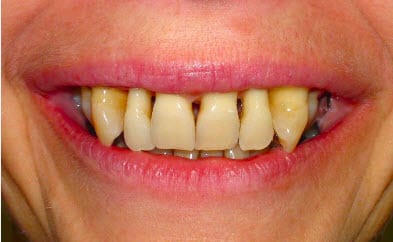

Dans ce cas-ci, quels arcs utiliseriez-vous pour ingresser les incisives et les canines ?

Pour ma part, je considère les bloc incisivo-canin comme mort sur le plan paro... Je suis pas sûr qu en ingressant tout ça on va gagner qqch

Sinon très beau sourire draculéen...

Tu gagnes rien, trop tard pour l'ortho .

Cette femme a 53 ans à 8 jours près. Elle souffre, on devrait quand même bien pouvoir trouver une solution orthodontique, non ?

Pourquoi dites-vous que ce serait trop tard pour de l'orthodontie ?

De 13 à 23, tu as beaucoup trop de perte osseuse pour faire de l'orthodontie. Le "trop tard" ne concernait pas l'âge de la patiente mais l'état de son parodonte.